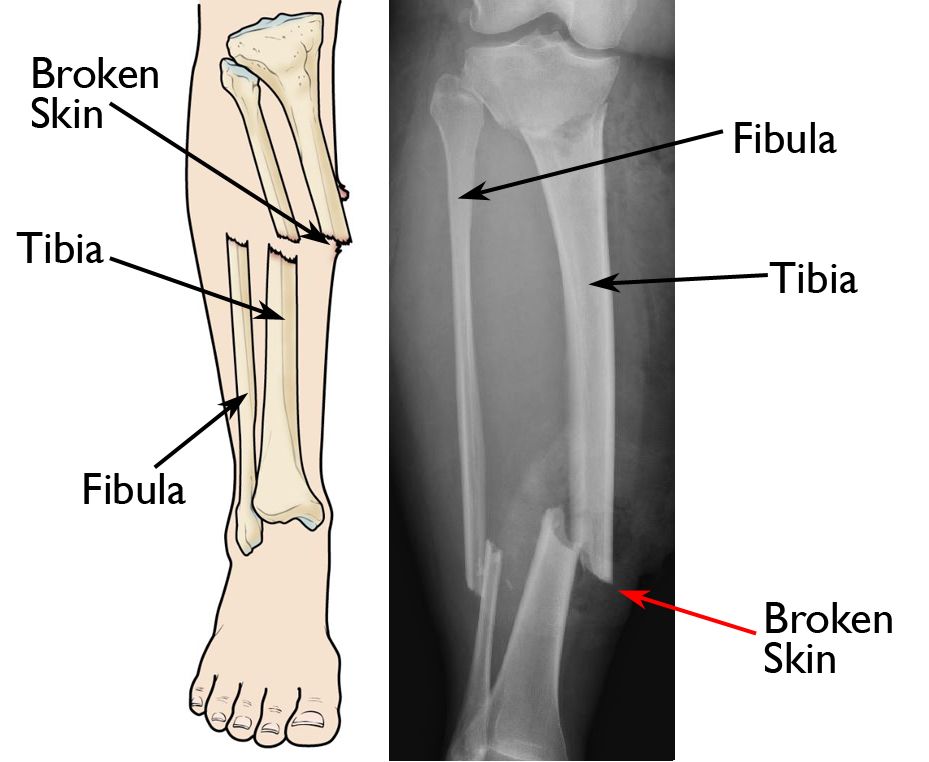

An open fracture

Illustration and X-ray show an open fracture. The broken end of the tibia (shinbone) has torn through the soft tissues and is sticking out through the skin.

(Right) Reproduced from Egol KA, Gardner MJ, eds: Let's Discuss Management of Common Fractures. Rosemont, IL, American Academy of Orthopaedic Surgeons, 2016, pp. 135-152.